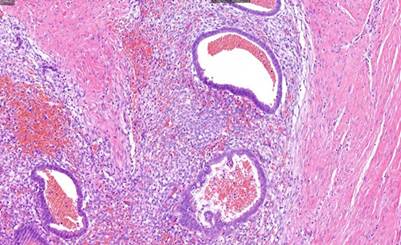

Respecto al caso 1, tras el análisis de la lesión, la descripción macroscópica coincide con un nódulo de tejido adiposo de 2 cm x 2cm que presenta áreas blanquecinas y otras rojizas al corte. Mientras que microscópicamente se describe como tejido fibroadiposo que incluye algunos fascículos nerviosos y estructuras vasculares, con numerosos focos de mucosa endometrial con glándulas focalmente dilatadas rodeadas por estroma celular y compacto. El diagnóstico final fue endometriosis subcutánea en relación con cicatriz de cesárea. Respecto a los resultados macroscópicos y microscópicos de los casos 2, 3 y 4, la conclusión respecto a su análisis acaba siendo, en todos los casos, lesiones nodulares de consistencia firme, de tamaños 2,5 cm x 2 cm; 6 cm x 6 cm, y 4 cm x 4 cm, respectivamente; con diagnóstico final de endometriosis cutánea, encontrándose tejido y estroma endometrial y glándulas, además de tejido hemorrágico, fibroso y adiposo (Figuras 3, 4, 5).

Figura 4 HE 21x. Glándulas endometriales dilatadas, revestidas por epitelio cilíndrico, que contienen material hemático en su interior. También se observa material hemático extravasado en el estroma circundante.